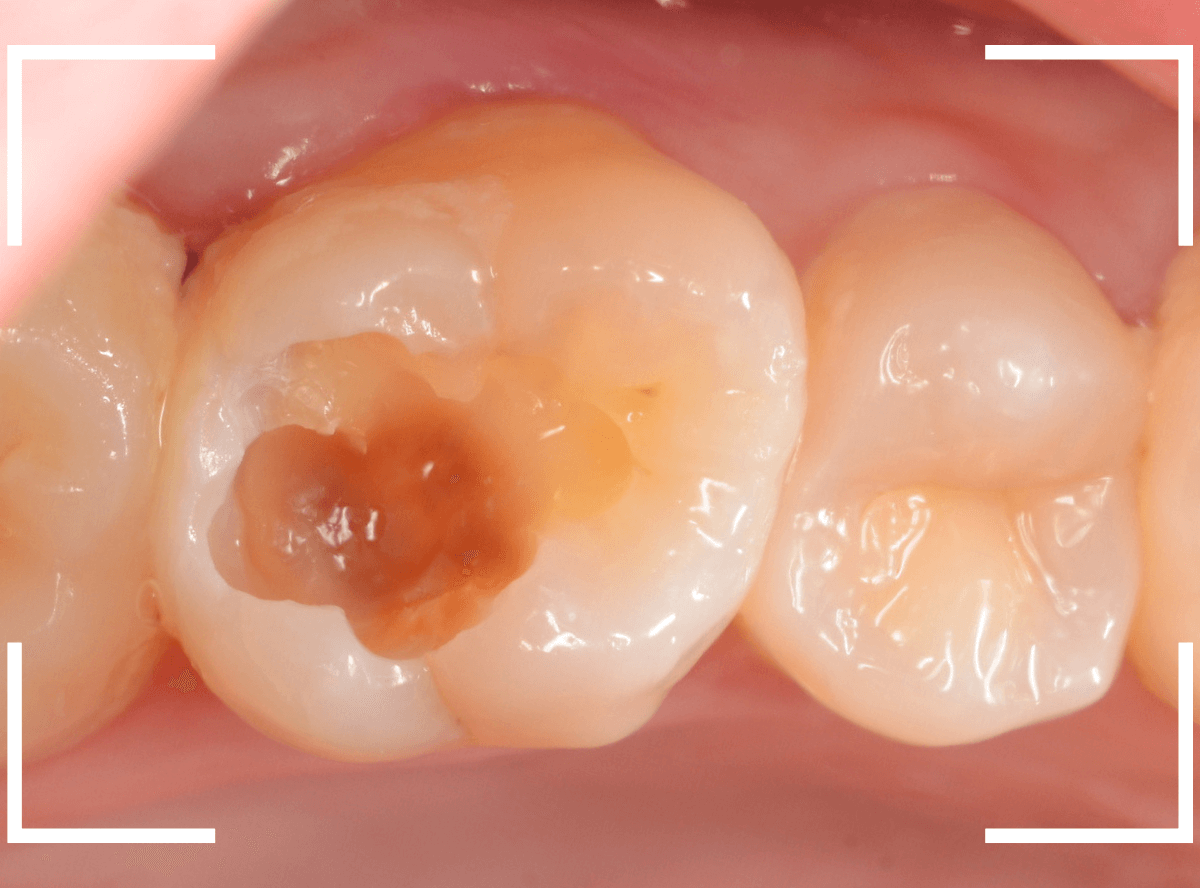

虫歯の治療を開始します。

隣の歯とのすき間を中心に広い虫歯になっていました。

虫歯治療後、特に症状もなく経過観察できましたので、つめものを作る治療に入ります。